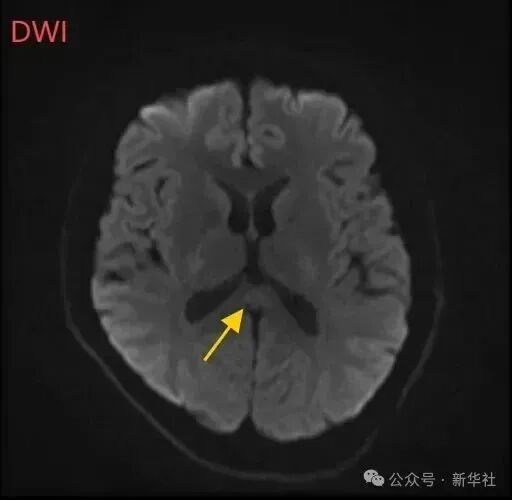

医生摇摇头,经过头部磁共振平扫、弥散、增强影像等检查,医生诊断,小董是得了一种比较少见的病症:可逆性胼胝体压部综合征。

小董的影像结果显示,胼胝体压部发生病变